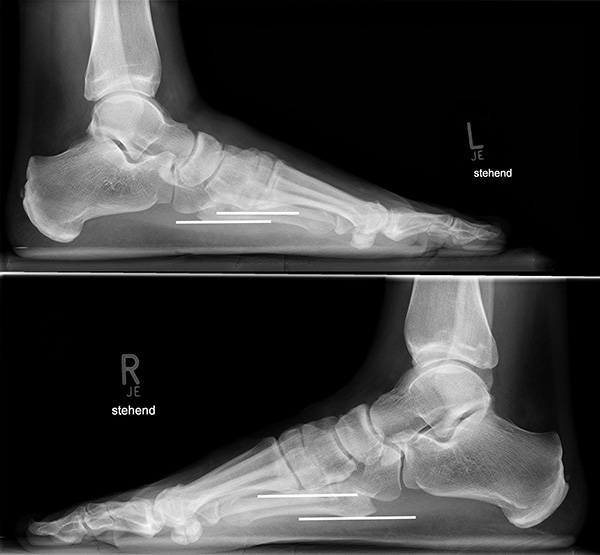

In der seitlichen Aufnahme ist auf Dislokationen und Subluxationen in den Tarsometatarsalgelenken sowie auf einen Verlust des Fußlängsgewölbes zu achten. Bei Instabilitäten des 1. Strahls bzw. Abflachung des Fußlängsgewölbes tritt in der Seitaufnahme die plantare Kontur des Os cuneiforme mediale tiefer im Vergleich zur Basis des Metatarsale 5. Darüber hinaus sollte die Cyma-Linie im Bereich des Chopartgelenkes in der Seitaufnahme eine harmonische S-förmige Linie bilden.

Insbesondere bei rein ligamentären, aber auch subtilen Verletzungen können belastete Vergleichsaufnahmen der unverletzten Gegenseite oder Streßaufnahmen des verletzten Fußes unter Bildwandlerkontrolle hilfreich sein 161129584 (Richter 2007).

Aber auch in den belasteten Röntgenaufnahmen sind subtile Frakturen und Luxationen oder rein ligamentäre Verletzungen oft nicht sicher darstellbar 7.

Zum Lesen der Bildbeschreibung und zur Vollansicht bitte das Bild anklicken.